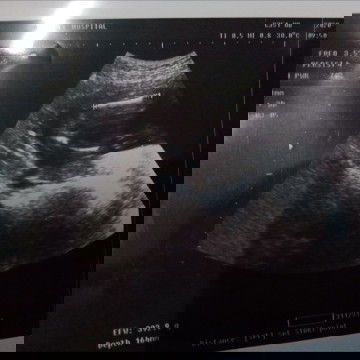

#ขอคำแนะนำหน่อยค่ะ แม่ว่า ญ รึ ช คะ พอดีหมอให้ใบซาวมา3 ใบ แต่แม่สะดุดใบนี้ หมอบอกว่าไม่มีไข่กะจู๋ หมอบอกว่าน้องนอนอ้าขาพอดี หมอบอกว่าน้องเป็น ญ แต่แม่กัวคลอดมามีไข่ อยากถามแม่ๆที่ได้ลูกสาว ว่า น้องเป็น ญ จริงไหม 20+1w #ขอบคุณล่วงหน้านะคะ